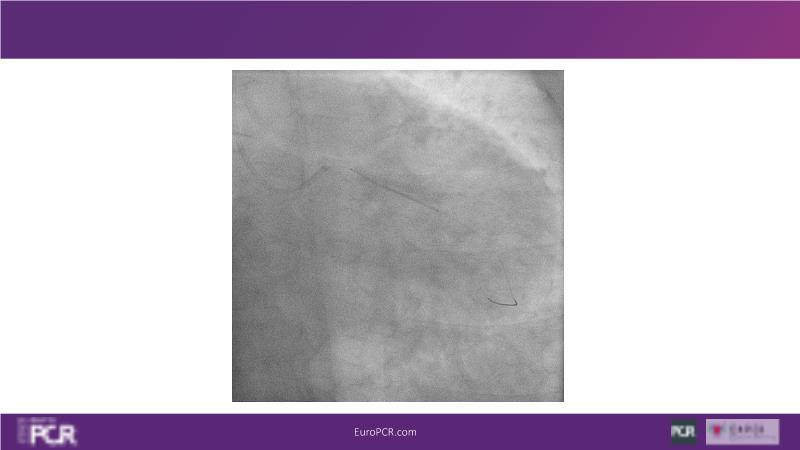

Join this session to explore the advantages of a fully optical approach in optimizing percutaneous coronary intervention (PCI) with the OptoWire III physiology wire and Nipro HF-OCT catheter. Through a practical case, you'll discover the significance of coronary physiology and intravascular imaging in bifurcation PCI and gain insights into how the performance and accuracy of the OptoWire III physiology wire can facilitate fast and reliable decision-making, particularly in side branch jailing scenarios.

- To discover the benefits of a fully optical approach to optimise PCI with OptoWire III physiology wire and Nipro HF-OCT catheter

- To review, through a practical case, the value of coronary physiology and intravascular imaging in bifurcation PCI

- To understand how the performance and accuracy of OptoWire III physiology wire can make the difference for fast and reliable decision-making in bifurcations, particularly through side branch jailing